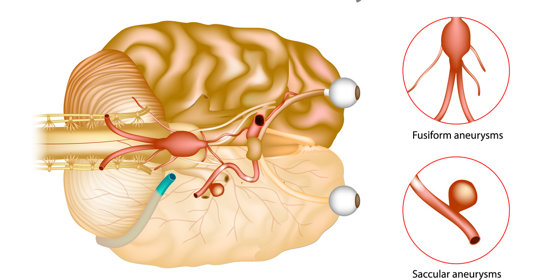

腦血管瘤手術後遺症的治療與預防:症狀、前兆與措施

腦動脈瘤破裂後遺症的防治與管理:症狀、前兆、治療與預防